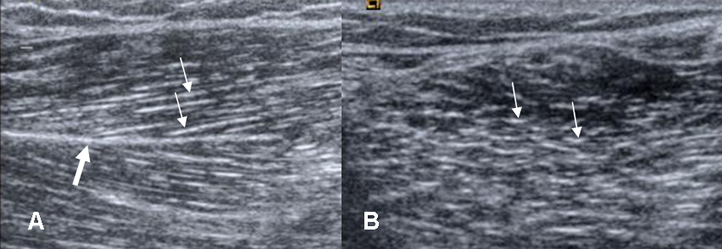

Fig 5. Músculo normal.

A: Ecografía corte longitudinal y B: corte transversal. Arquitectura normal, con perimisio ecogénico (Flechas delgadas). También se identifica un septo intramuscular ecogénico (Flecha gruesa).